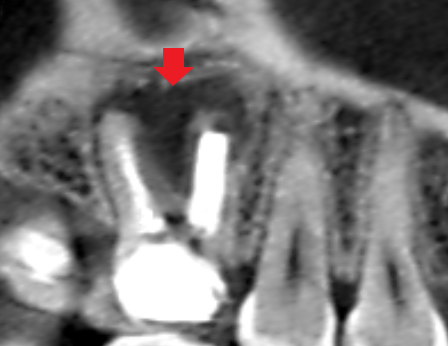

実際に「根管」の画像をご覧頂きましょう。歯の中にある黒い筋が根管です。